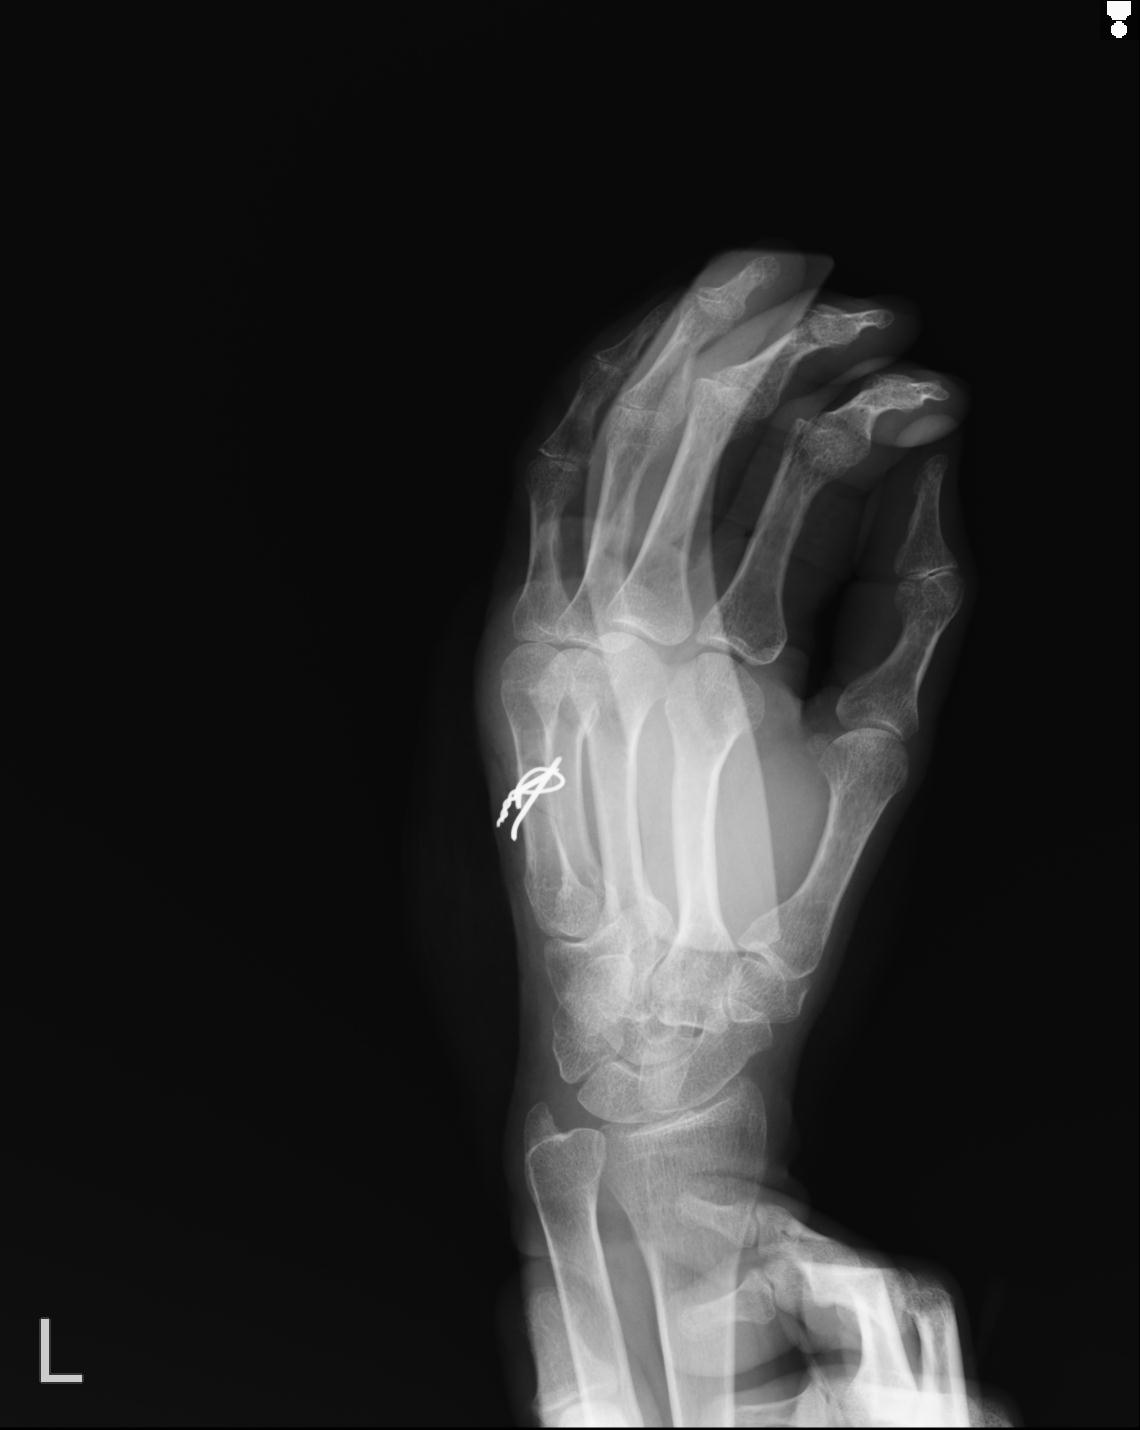

102766 1/5 1/12 左手関節 4R 28歳男性 左橈骨遠位端